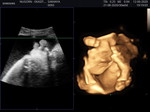

น้องคลอดแล้ว 38+3

น้องมีปัญหาหายใจเร็วผิดปกติ ตอนนี้หมอใส่ออกซิเจน ตั้งแต่ออกมาเจอลูกแค่แปปเดียว บ้านไหนมีปัญหาแบบนี้บ้างแนะนำหน่อยค่ะ ห่วงลูกมาก